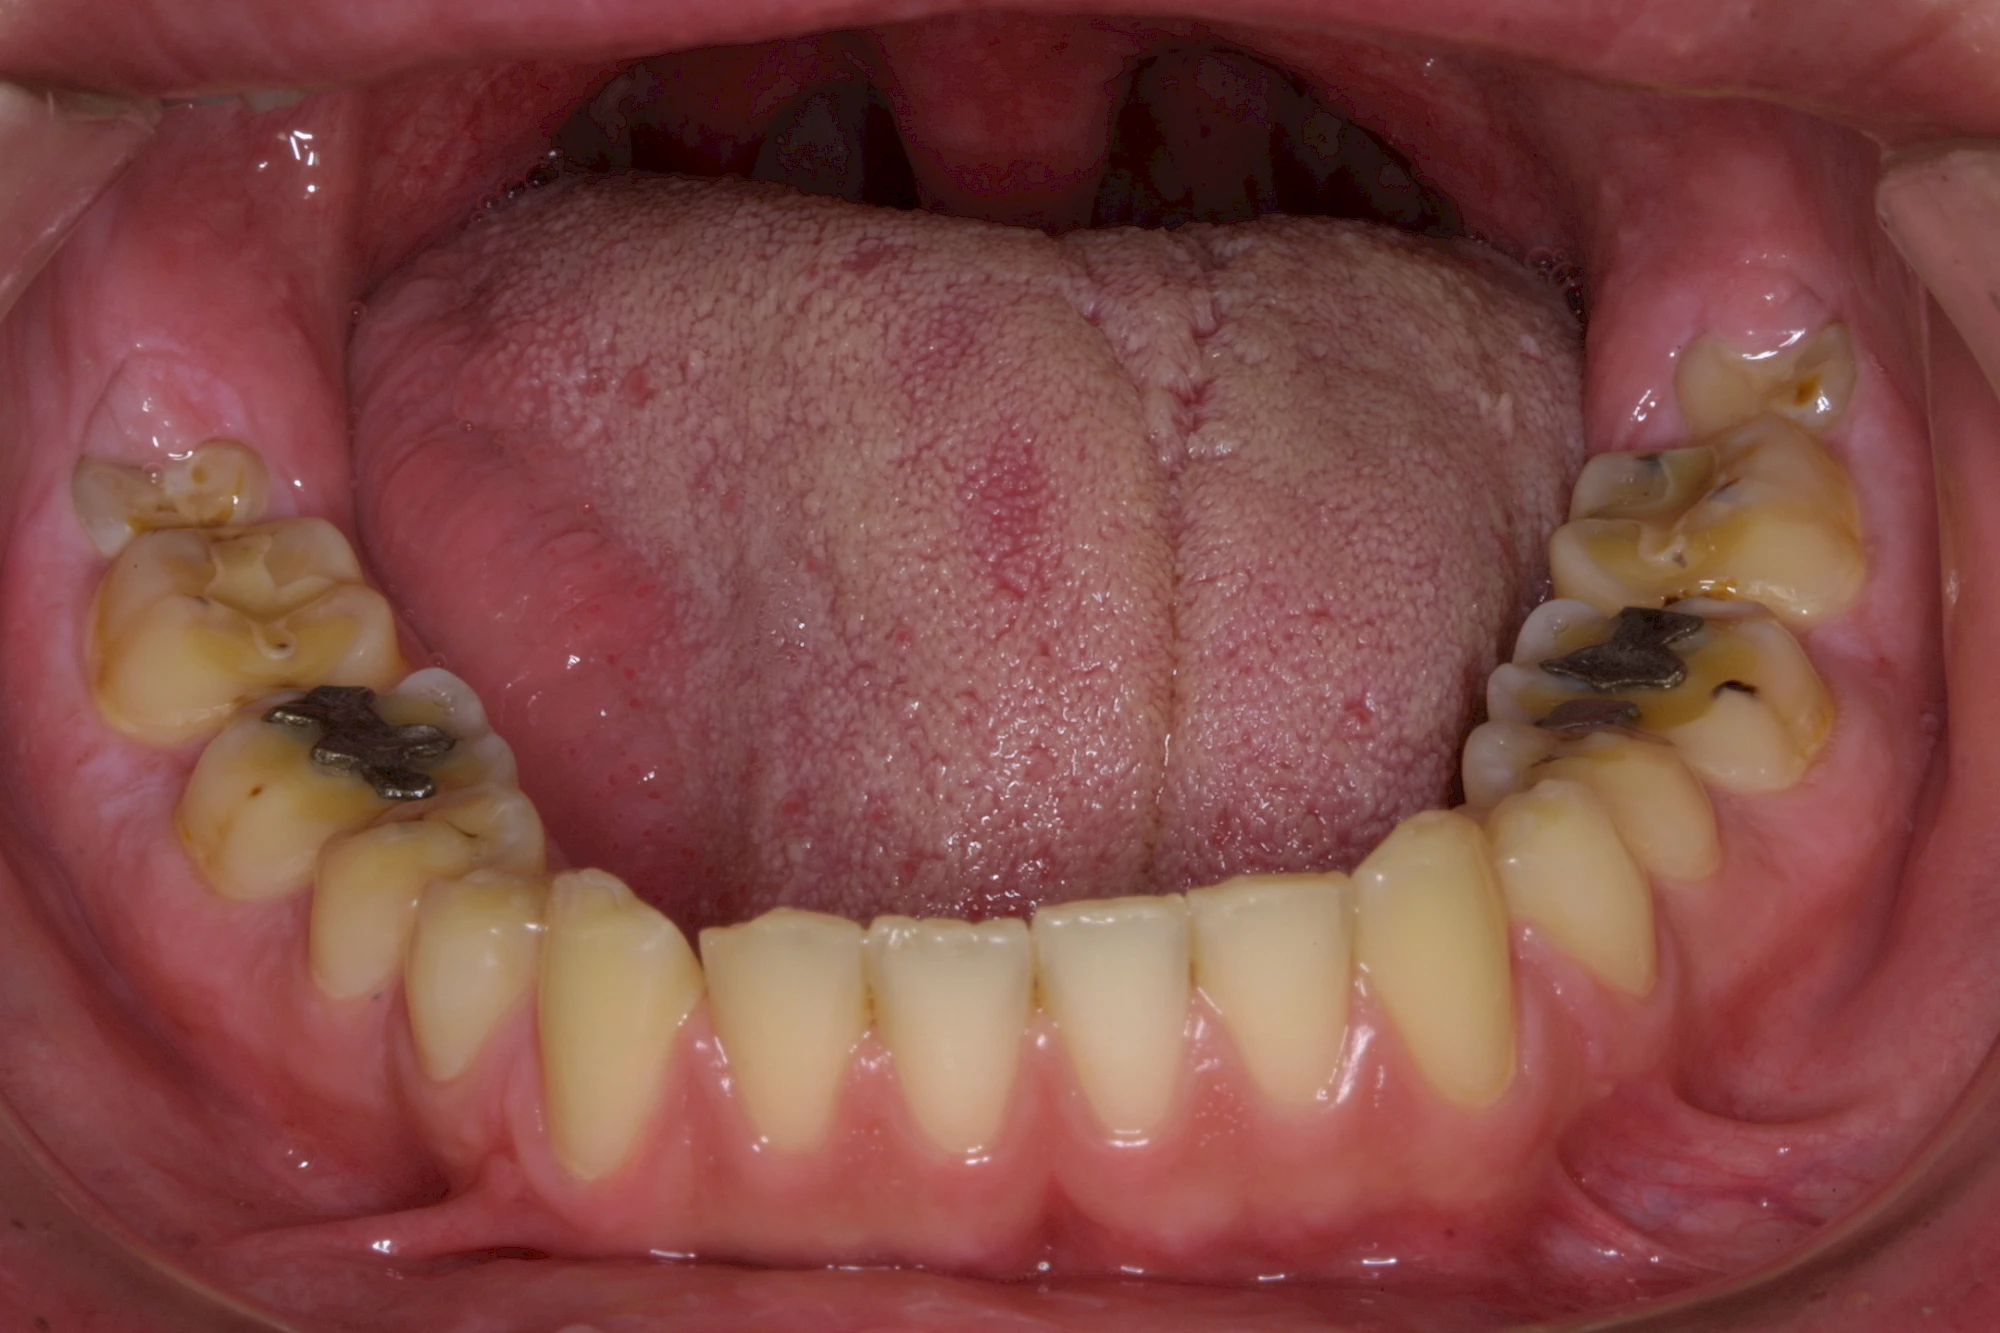

Über die Zeit können verschiedene Prozesse die Zahnhartsubstanzen aufzehren:

- Abnutzung durch Kauen (Abrasion) oder duch durch übermäßiges Knirschen bzw. Pressen (Attrition)

- Säurebedingte Auswaschung (Erosion)

- Knirschen bzw. Pressen und ungünstige Putztechnik (Druck): keilförmige Defekte

Die Zähne können dabei auf Reize (warm, kalt, süß, sauer) oder auch beim Zähneputzen empfindlich oder schmerzhaft sein. In allen diesen Fällen ist es sinnvoll, den Zahnarzt zu kontaktieren und das weitere Vorgehen abzustimmen.